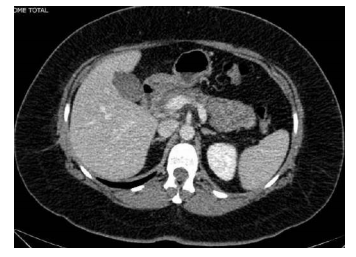

Um paciente de 51 anos de idade, sem comorbidades, iniciou, há três dias, quadro de fortes dores em hipocôndrio direito e epigástrio, com vômitos após refeição copiosa. Fez uso de analgésicos comuns, mas, como houve piora da dor, procurou o atendimento do seu médico particular. O médico solicitou exame de imagem e exame laboratorial para investigação. Nos exames laboratoriais, Hb 13 g/dL, leucócitos 14.000/mm3 , TGO e TGP dentro da normalidade, bilirrubina total 3,2 mg/dL, bilirrubina direta 2,8 mg/dL, amilase 650 U/L, ureia 28 mg/dl, creatinina 1,2 mg/dL, fosfatase alcalina 110 mg/dL, gama GT 320 mg/dL e PCR 5 mg/dL. Realizou uma ultrassonografia, que revelou colelitíase, e a tomografia cuja imagem é mostrada a seguir. Após avaliar os exames, o médico encaminhou o paciente ao pronto-socorro.

Com base nesse caso hipotético, assinale a alternativa correta.